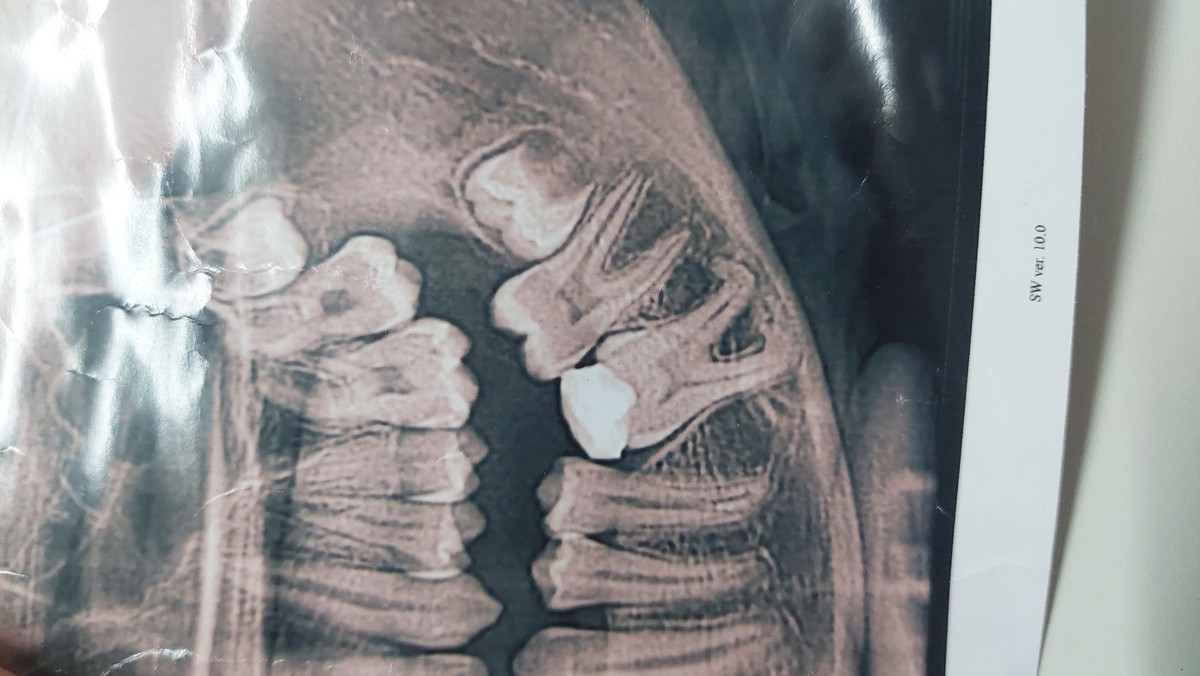

Не рекомендую! 6 лет наблюдались у этого врача, исправляли прикус у ребёнка! Всё шло хорошо до определённого момента , а именно до октября 2025 года. Когда пришли на плановый осмотр , Яна Олексеевна сказала сделать снимок так как ей не понравился один зуб .хорошо....поехали сделали и пришли на повторный приём . С её слов у ребёнка в 12 лет остался молочный зуб и срочно его удалять, я смотрела на её реакцию и понимала что что то не так. Этот зуб перед войной она рекомендовала залипить пломбой так как верхний на против него активно рос и чтоб не вырос больше положенного она выбрала такой вариант! Я помню это как сейчас. Ну ок..... поехали мы ещё на консультацию к двум артодонтам и они были в ужасе как так можно было испортить ребёнку зуб и причём постоянный. Загнутые корни которые в миллиметре от лицевого нерва. Итог по её вине у ребёнка не вылез взрослый зуб, теперь его тянуть специальной системой и дай бог получится и второе чтоб скрыть свою ошибку отправила к своему же хирургу удалять целый и постоянный зуб под видом молочного. Все снимки и КТ имеются . Крайне не рекомендую!